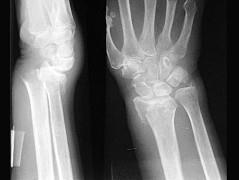

问题 图示骨折,下列哪项是错误的 ( )

选项 A、多由间接暴力发生骨折 B、骨折发生在桡骨下端3cm范围内 C、常合并下尺、桡关节脱位及尺骨茎突骨折 D、有典型畸形,正面可见典型的“银叉”畸形 E、多见于成年及老年人

答案 D